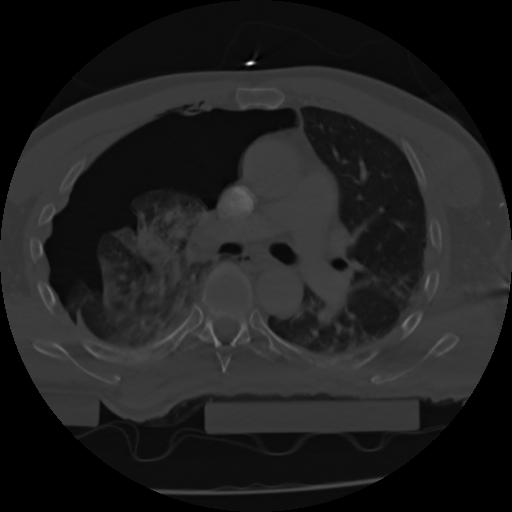

21 ANGIO,CE,Axial,3.0,ANGIO,,